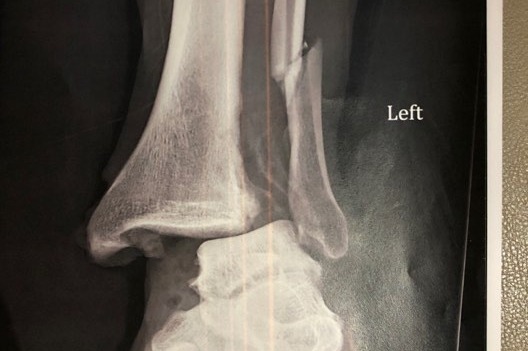

His left ankle bone was out.

After breaking the line, he got tackled from behind and the force dislocated his ankle, fractured his fibula and shredded multiple ligaments.